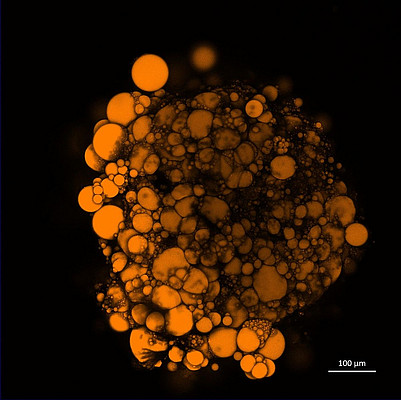

To overcome these limitations we establish three-dimensional immune cell containing organoids.

The 3D-cell culture is performed in a 96-well plate format and is easy accomplished, offering the potential for high throughput experiments.

The formation of adipose and cardioid organoids will potentially help in the future to answer questions regarding cardial immunity, obesity, diabetes and many more pathological conditions connected to cardiac and metabolic related diseases.